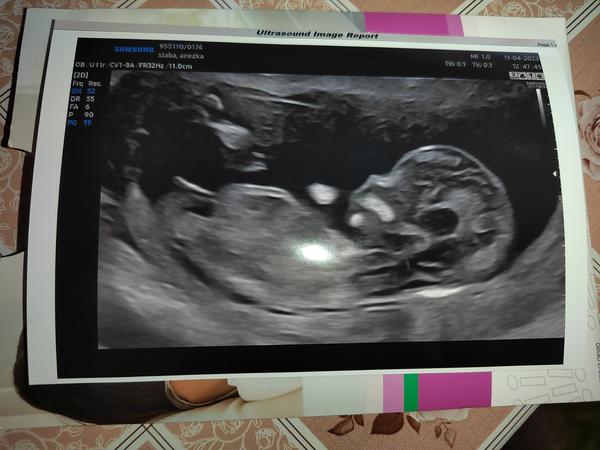

Dobrý den, oživuji diskuzi ❤️ 11tt, je to jen screenshot z videa které jsem si natočila na mobil, tak bůh ví, zda jsem to cvakla v dobrou chvíli a není to klamavé 😄 Co myslíte? Do prenatalu jdeme až 6.11. a já mám pocit že prasknu nedočkavostí, jsem zvědavec hrozný 🙈 Toť otázka - pohlavní hrbolek, nebo jsou to kulky, nebo konec kostrče? Co myslíte, jen tak pro srandu? Přáli bychom si holku, ale kdyz jsem videla prvni pohyby na UTZ v 11+1, tak jsem si uvědomila že ať bude co bude, budu mimi milovat uplne stejne bez rozdílu ❤️ Je to mazec!!